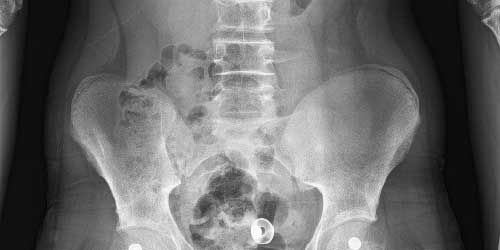

- Düz grafi: Düz radyografi, pediküllerin veya omur gövdesinin erozyonunu göstermek için kullanılır. Bununla birlikte, radyolojik bulgular sadece kemik yıkımı% 30-50'ye ulaştığında ortaya çıkmaktadır.

- Bilgisayarlı tomografi (BT) taraması. MRG yumuşak dokuları daha ayrıntılı gösterirken BT kemik yapıları göstermede daha üstün ve kullanışlıdır. BT taraması MRG ile kombinasyon halinde kullanılabilir. Ayrıca nereden kaynaklandığı bilinmeyen metastaz hastalarında primer odağı saptamak için akciğer, karın (batın) tomografisi çekilir. Metastatik hastalarda başka bir omurga lokalizasyonunda da lezyon olabilme ihtimalinden dolayı (%15) görüntüleme yöntemleri tüm omurgayı içerecek şekilde çekilmelidir.